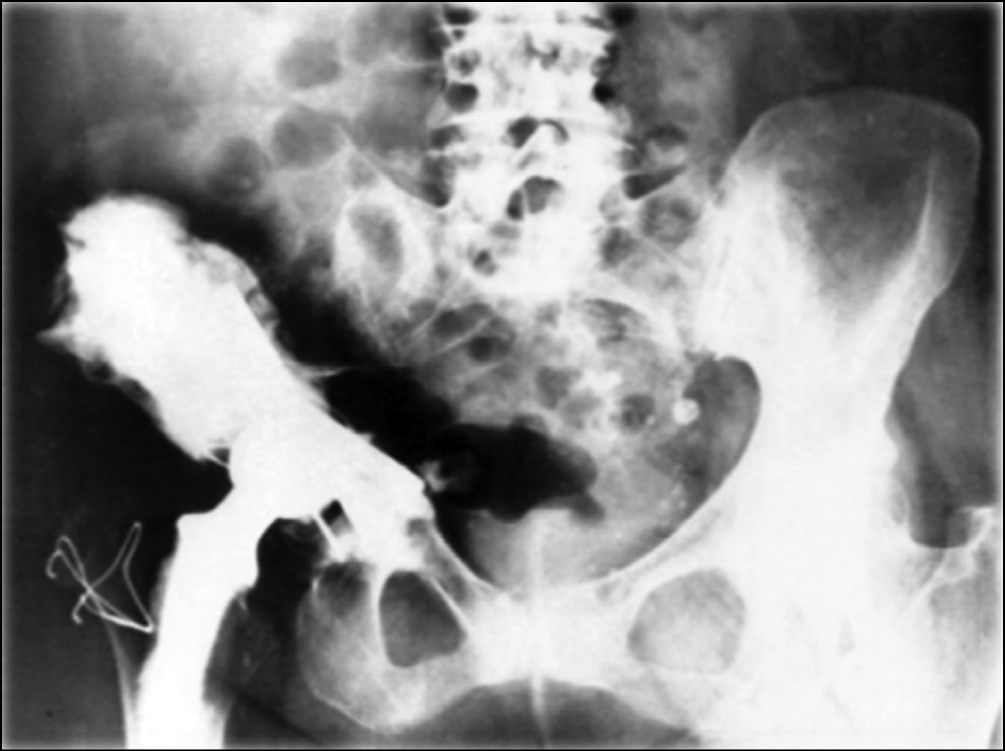

В клинике университета Южной Калифорнии (США) в период с 2000 по 2009 г. 25 пациентам с опухолевым поражением параацетабулярной области имплантированы модифицированные «седловидные» эндопротезы (рис. 5) [33]. Средний период наблюдения составил 29 мес. За время наблюдения прогрессирование заболевания выявлено у 15 (60 %) больных.

Рис. 5. Периацетабулярная реконструкция с применением «седловидного» эндопротеза: а — внешний вид; b — рентгенограмма костей таза, после выполненной операции. Металлоимплант фиксирован к резецированному крылу подвздошной кости [33]

Общее количество значимых осложнений — 11 (44 %). Глубокое инфицирование раны — у 6 (24 %), вывих протеза — у 3 (12 %) и перелом подвздошной кости с транспозицией эндопротеза — у 2 (8 %) пациентов. Среднее значение функционального результата по шкале MSTS составило 67 %.